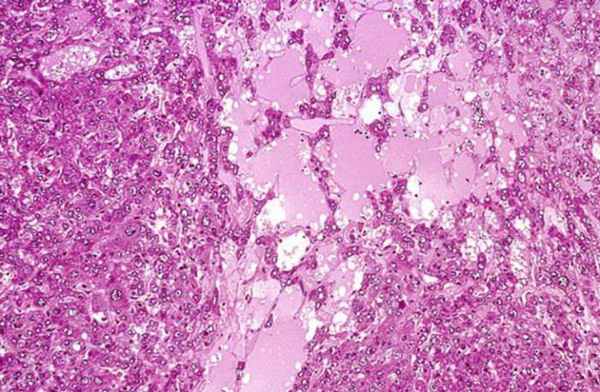

Гиперфлуоресцирующие области клеток пигментного эпителия заметны лишь в зонах атрофии сетчатки. При гистологическом исследовании центральной зоны глазного дна выявляется излишнее количество липофусцина. Клетки пигментного эпителия гипертрофированы и атрофированы в комбинации.